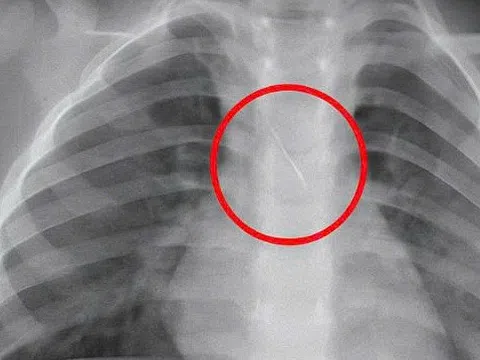

Tại đây, qua thăm khám lâm sàng và chẩn đoán hình ảnh, bác sĩ xác định bệnh nhân bị vỡ bàng quang trong phúc mạc, kèm chấn thương gan độ I.

Ê-kíp Ngoại niệu - Ghép thận - Nam khoa đã nhanh chóng phẫu thuật khâu phục hồi bàng quang hai lớp, đặt dẫn lưu ổ bụng và sonde tiểu lưu. Về phần gan, ê-kíp Ngoại Tổng hợp thăm khám và quyết định điều trị bảo tồn.

Vỡ trong phúc mạc (khoảng 30%): thường gặp khi bàng quang căng đầy, bắt buộc phải phẫu thuật khâu phục hồi.Vỡ ngoài phúc mạc (60%): thường đi kèm gãy xương chậu, có thể điều trị bảo tồn ở trường hợp nhẹ.Vỡ phối hợp (10%): phức tạp hơn, buộc phải can thiệp ngoại khoa.Theo bác sĩ Phong, nhiều ca bệnh liên quan trực tiếp đến việc uống rượu bia rồi nhịn tiểu. Khi đó, bàng quang căng quá mức, chỉ một va chạm hoặc cú ngã nhẹ cũng có thể dẫn đến vỡ.